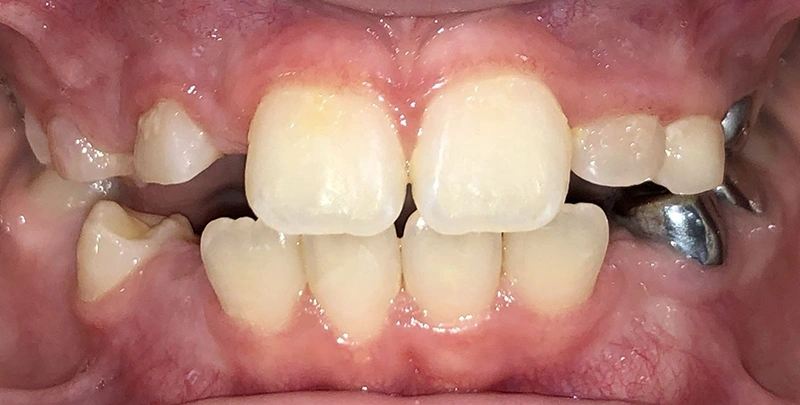

Actual Patient: Victoria

Img Before 1 1 Img After 1 1

Severe Crowding, Narrow Jaws, Severe Deep Bite

image 1 after img

Treatment Time:

8 months

Front View

Top View

Right & Left Sides